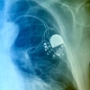

Egy 83 éves amerikai férfit a 240 voltos áramütés következményétől óvta meg a mellkasába beoperált pacemaker, mert visszaütött.